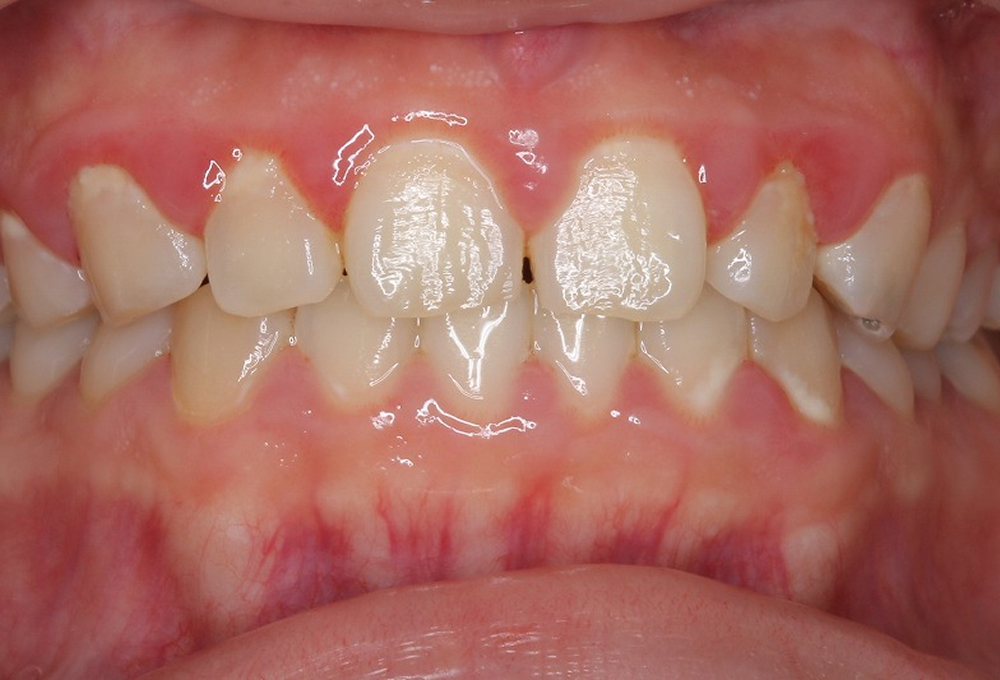

①術前 プラークコントロール不良のため歯肉炎